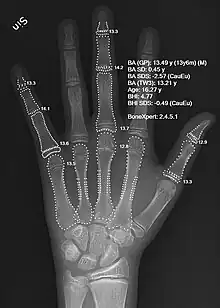

Since bone maturation is a good indicator of overall physical maturation, an x-ray of the left hand and wrist to assess bone age usually reveals whether the child has reached a stage of physical maturation at which puberty should be occurring.[3][7] X-ray displaying a bone age <11 years in girls or <13 years in boys (despite a higher chronological age) is most often consistent with constitutional delay of puberty.[7][40] An MRI of the brain should be considered if neurological symptoms are present in addition to delayed puberty, two findings suspicious for pituitary or hypothalamic tumors.[3][10] An MRI can also confirm the diagnosis of Kallmann syndrome due to the absence or abnormal development of the olfactory tract.[10] However in the absence of clear neurological symptoms, an MRI may not be the most cost-effective option.[10] A pelvic ultrasound can detect anatomical abnormalities including undescended testes and müllerian agenesis.[3][39]